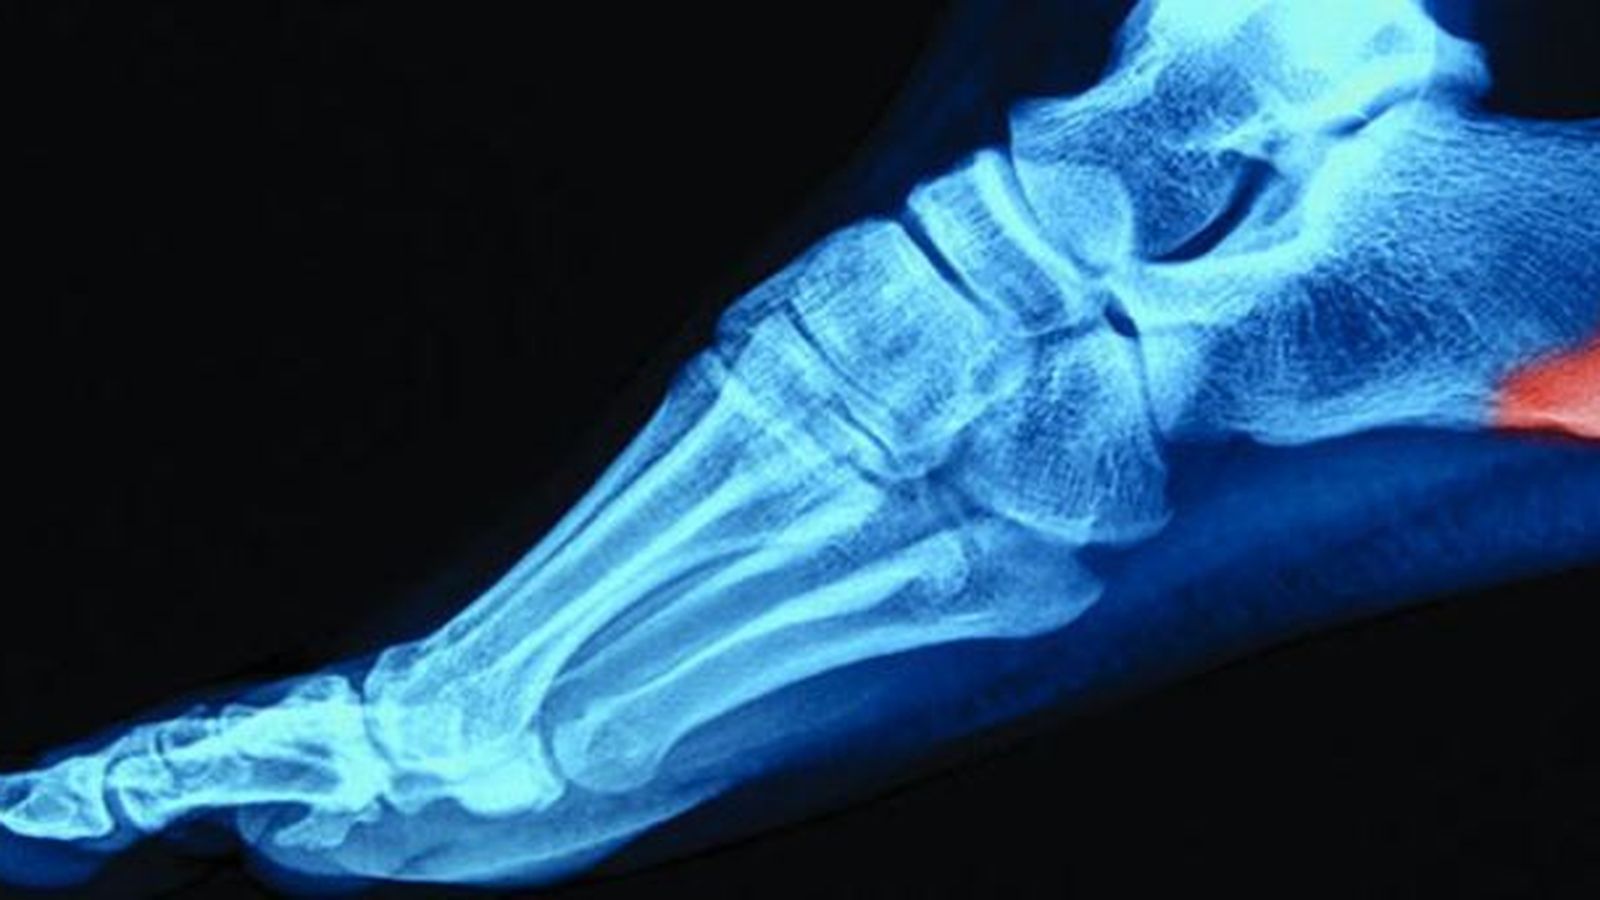

Hallux valgus o juanete

Es un cuadro que cursa con una desviación lateral del dedo gordo en la unión con la articulación metatarsofalángica del pie. La parte interna de la cabeza del primer metatarsiano presenta una prominencia que se llama bunion y que se puede irritar o enrojecer por el calzado. El resto de los pies se pueden deformar, adoptando la forma de dedos "en martillo". Estos dedos martillo suelen provocar dolor y forman callosidades en el dorso del dedo al rozar con el zapato. El juanete junto con el pie plano, es la causa más frecuente de deformidad en los pies.

Es más frecuente en mujeres que en hombres, en una proporción de 10/1. Puede haber cierta predisposición familiar a la hora de padecerlos (madres con juanetes, hijos con juanetes). Sin embargo, lo más frecuente es que su aparición se deba al uso de calzado excesivamente estrecho o de tacón; esto provoca una presión continua del dedo gordo hacia el quinto dedo, provocando que la cápsula y los ligamentos que rodean y estabilizan al primer dedo cedan y se produzca la deformidad, poco a poco. En otras ocasiones, algunas enfermedades reumáticas o artrosis entre las más frecuentes pueden provocar o acelerar su aparición.